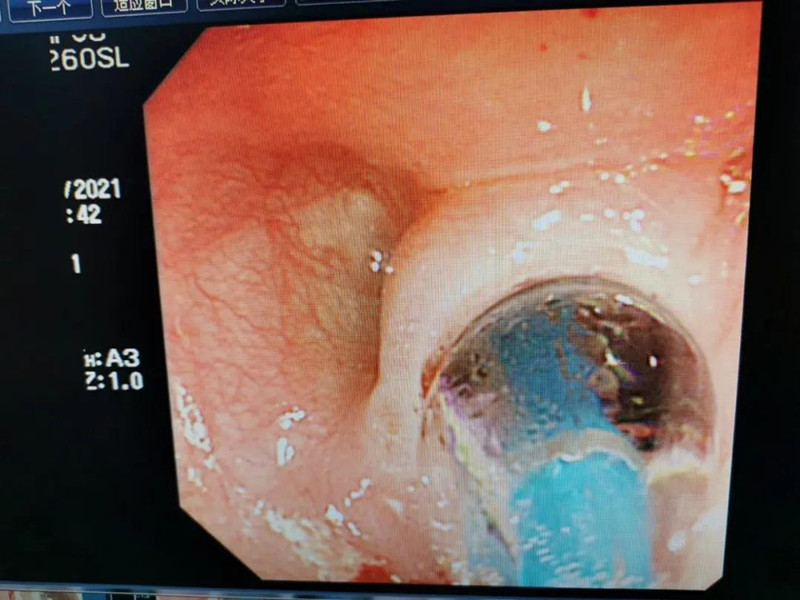

天天6个月了。最近总出现呛奶的情况,后来还出现肺炎症状。在德州扑克游戏网 经食道造影后,医生发现天天的症状是由术后并发症“食道吻合口狭窄”引起的,最窄处仅5mm多一点。食道狭窄球囊扩张术是目前最适合天天的手术了。内镜中心副主任边鹏说,这是一种微创介入治疗,具有创伤小、恢复快、合并症少的优势。2月26日,在麻醉科、内镜中心团队的合作下,边鹏为天天行经内镜下食道狭窄球囊扩张术。术中,边鹏用直径8mm的球囊进行扩张,将原来狭窄的食道扩成直径8mm的宽度。

天天太小,在球囊扩张的过程中,需要格外注意,不能扩张太快,否则会出现穿孔或大出血。所以边鹏每扩张3分钟,暂停3分钟,共扩张了3次。整个扩张过程很顺利,效果也非常好。次日,天天就出院了。在球囊扩张前,小儿内镜下显示,天天食道吻合口狭窄处上端竟有一团纸,家长也不清楚孩子是什么时候吃了纸。因为吻合口处太窄,纸下不去,形成了阻隔,导致天天最近总呛奶,奶汁进入气道,最终出现肺炎。